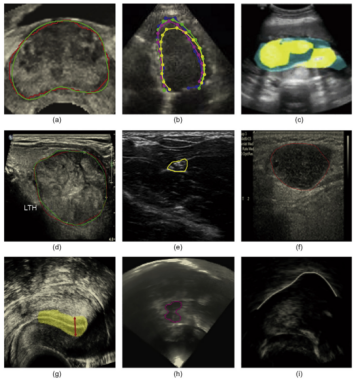

AI医学影像,也称为辅助诊断AI,是指利用人工智能技术处理和分析医学影像数据,以辅助医生进行疾病诊断和治疗方案制定的技术。其主要原理是通过机器学习和深度学习算法,使计算机能够学习和理解医学影像中的特征和模式,并提供对患者疾病状态的预测和评估。AI医学影像是AI医疗领域目前最为成熟和常见的领域之一。

1、详细科普医疗图像主要类型,X 射线成像原理、CT 断层扫描机制、MRI 磁共振成像特色、超声成像的声波利用。

深度学习在医疗图像分析中的应用

2、结合案例,剖析深度学习在图像分类、目标检测、分割中的应用流程,实操演示常用深度学习模型 YOLOv5 在医疗图像里的调用与优化。

1、以肺结节筛查诊断为切入点,展示图像分析辅助医生精准定位、良恶性判断流程。

2、延伸至肿瘤识别与分割,讲解如何利用图像处理技术勾勒肿瘤边界;探讨心血管疾病诊断评估,通过血管影像分析病情。